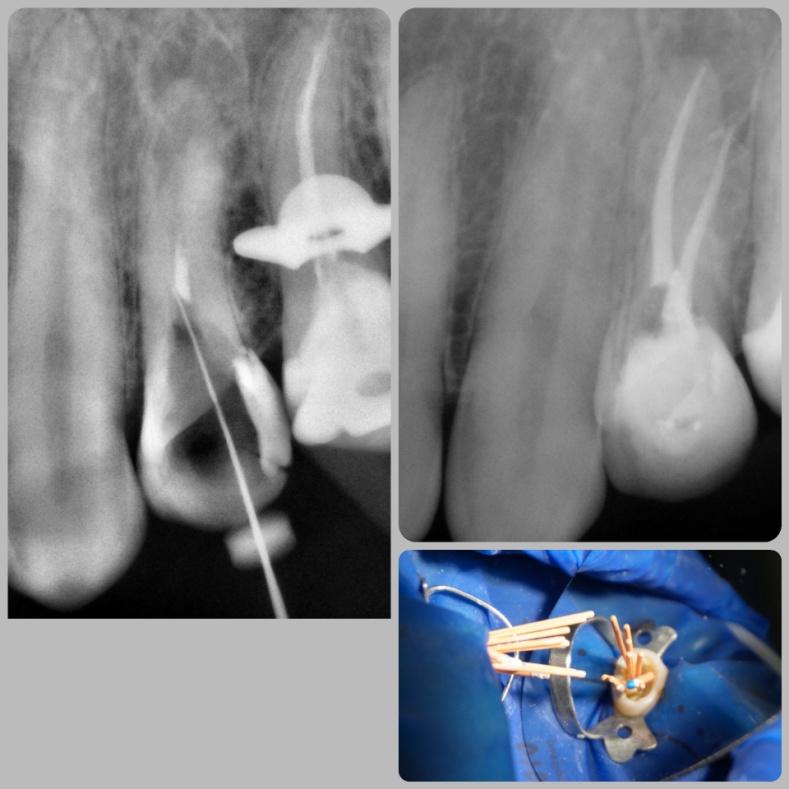

Leczenie kanałowe pierwotne

Konserwatywne leczenie torbieli korzeniowej (reendo – powtórne leczenie kanałowe).

Efekt po 6 miesiącach.

lek. stom. Aleksa Mucha

Zgodnie z zasadą, że prace protetyczne powinny być oparte na zdrowych i solidnych fundamentach, zaczęłyśmy od podstaw – wymiana nieszczelnych wypełnień, powtórne leczenia kanałowe.